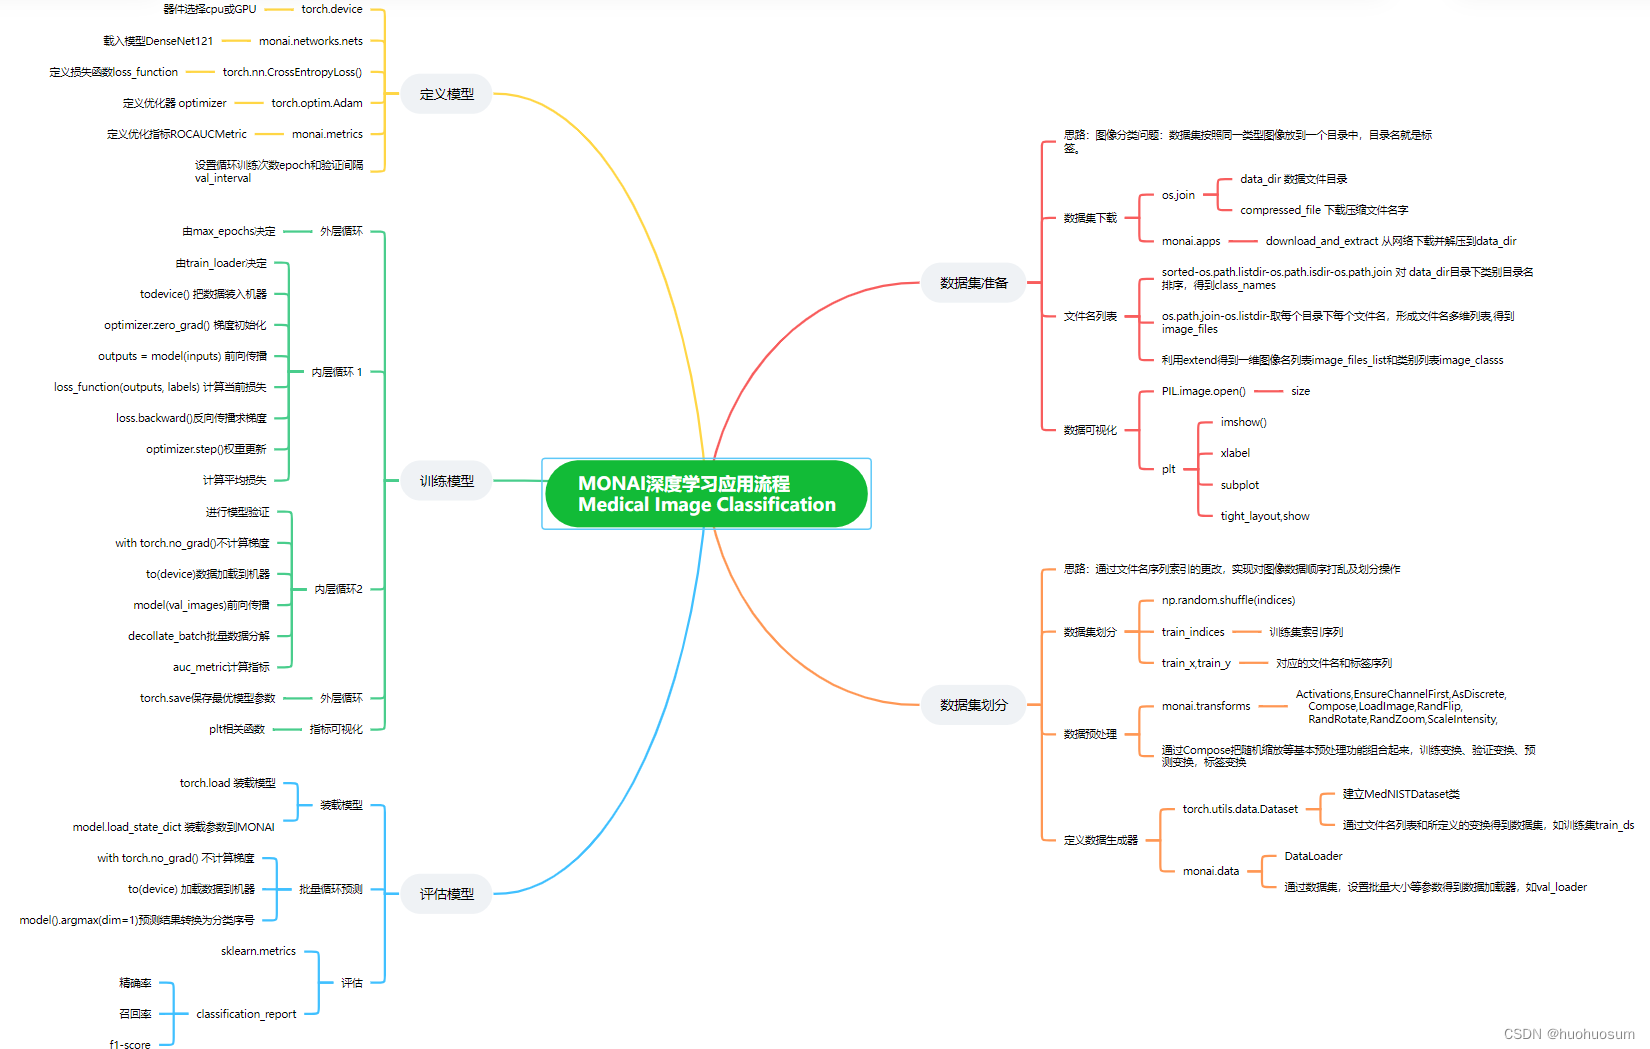

2 例程代码总结

上图对例程代码进行了归纳,基于DenseNet121模型训练与评估过程分为五个阶段:

- 数据准备

利用monai框架函数down_and_extract从网络下载并提取数据集,数据集分为6个文件夹,每个文件夹包含了一类图像数据。再利用os软件包的listdir等函数,结合列表表达式得到文件名列表和标签列表。在深度学习框架中,一般通过对文件名列表的操作,实现对数据的排序和数据集划分等操作。 - 数据集划分

借助索引,先通过对文件名列表和标签列表操作,划分训练集、验证集和测试集;再借助monai框架的transformm函数定义三种数据集上采用的不同变换;最后定义monai数据集和数据加载器。 - 定义模型

通过torch框架和monai框架的函数,完成模型、损失函数、优化算法的定义。 - 训练模型

按照torch的训练与验证步骤,对所有样本以批量方式进行训练。模型训练包含前向传播、反向传播、损失计算和权重更新等过程;而模型验证无需计算梯度,只包含前向传播和交叉熵计算过程。所有训练完成只有,保存最佳模型参数。 - 评估模型

评估模型采用测试数据集,先加载最优模型,进行前向传播得到预测值,再通过sklearn框架函数计算预测结果的精确率、召回率和f1-score等指标,全面评估模型性能。